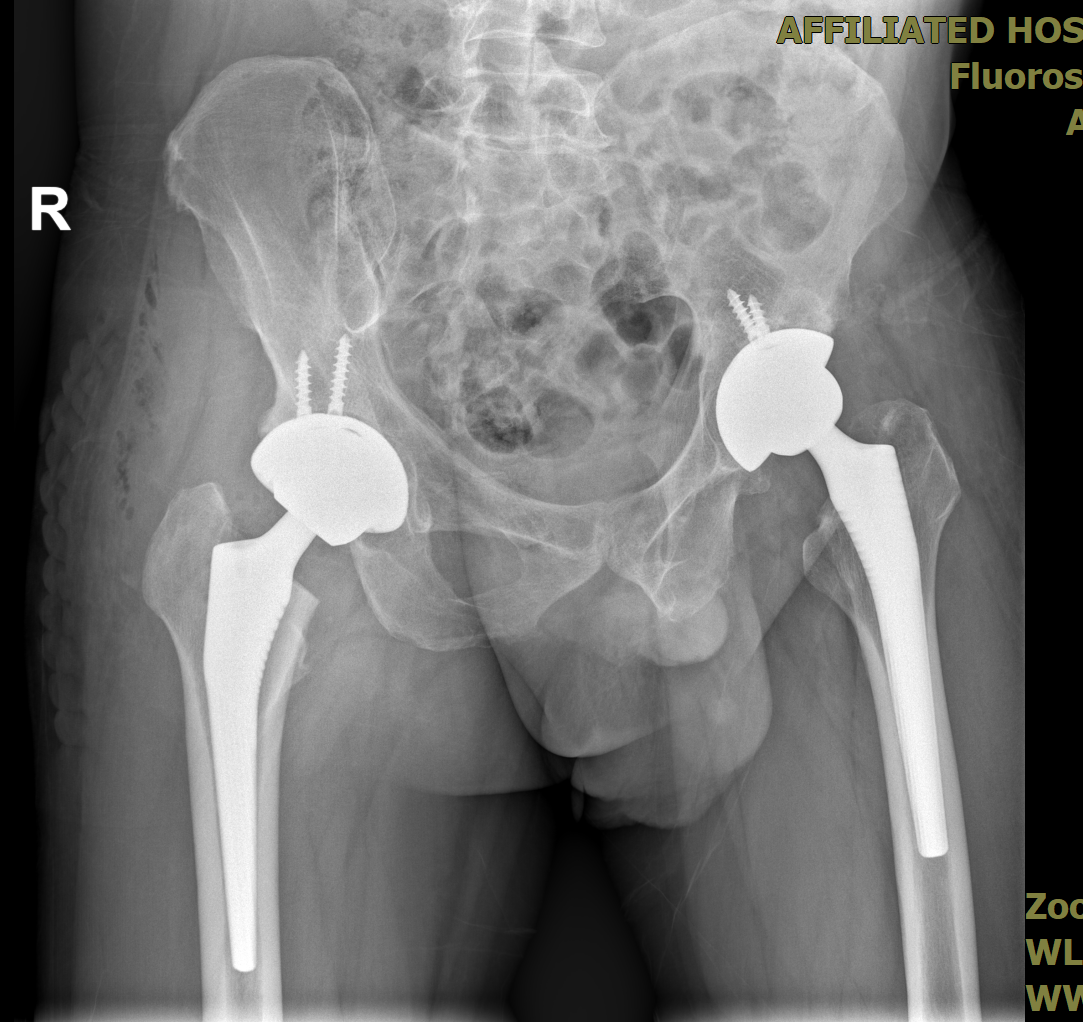

自体骨深低温储存后行右侧骨缺损移植及右人工全髋关节置换术。骨缺损移植手术过程中,在自体骨专业储存机构(四川骨源生物科技有限公司)的技术支持下,将经过深低温储存的自体骨精准移植于右侧髋关节的缺损部位,借助自体骨组织的生物相容性和骨传导性促进骨组织的愈合。该手术方案无需额外进行取骨操作,从而减少了手术创伤,降低了患者的痛苦和风险。

手术整体过程顺利,患者术后恢复情况良好,右侧髋关节功能逐渐恢复正常。在术后随访过程中,未发现感染或排异反应等并发症。影像学复查结果显示,双侧关节对应未见异常,患者及其家属对此次手术效果表示高度满意。

右人工全髋关节置换及右侧骨缺损移植术后